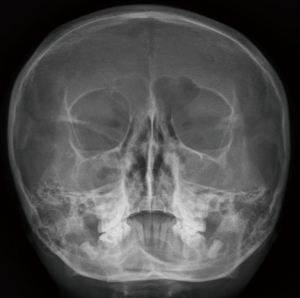

Initial laboratory findings, including complete blood count, liver function tests, CRP, amylase, and lipase, were unremarkable with a normal eosinophil count (4.3%, 450/µL). Fecal immunochemical testing was positive, and the fecal calprotectin (FC) level was 673 mg/kg. No pathogens were detected in stool culture or by multiplex polymerase chain reaction (PCR) (Seegene Inc.). Water’s view radiography demonstrated right frontal and bilateral maxillary sinusitis (Figure 1). Plain chest radiography demonstrated suspicious bronchiectatic lesions in both lung fields (Figure 2). Chest computed tomography (CT) demonstrated subsegmental atelectasis in the right middle lung field and diffuse bronchiectasis in both lungs (Figure 3). Abdominal CT and magnetic resonance (MR) enterography showed diffuse wall thickening from the distal ileum to the ascending colon. Pancreatic atrophy with diffuse calcification was observed with peripancreatic fat infiltration indicated chronic inflammation (Figure 4).